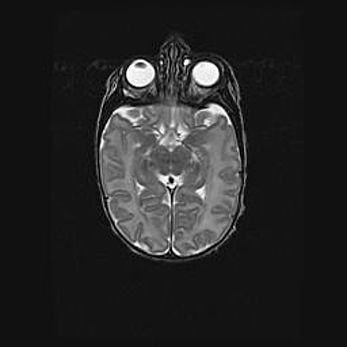

Церебральная ишемия II.

Возраст: 5 дней

Вес: 3400 г

Пол: женский

Окружность головы: 35 см

Срок гестации: 39 недель

Церебральная ишемия – это заболевание, характеризующееся недостаточностью (гипоксией) либо полным прекращением (аноксией) снабжения мозга кислородом по причине закупорки одного или нескольких сосудов. Это приводит к  что метаболическим расстройствам различной степени тяжести в тканях головного мозга, развитию коагуляционных некрозов и гибели нейронов.